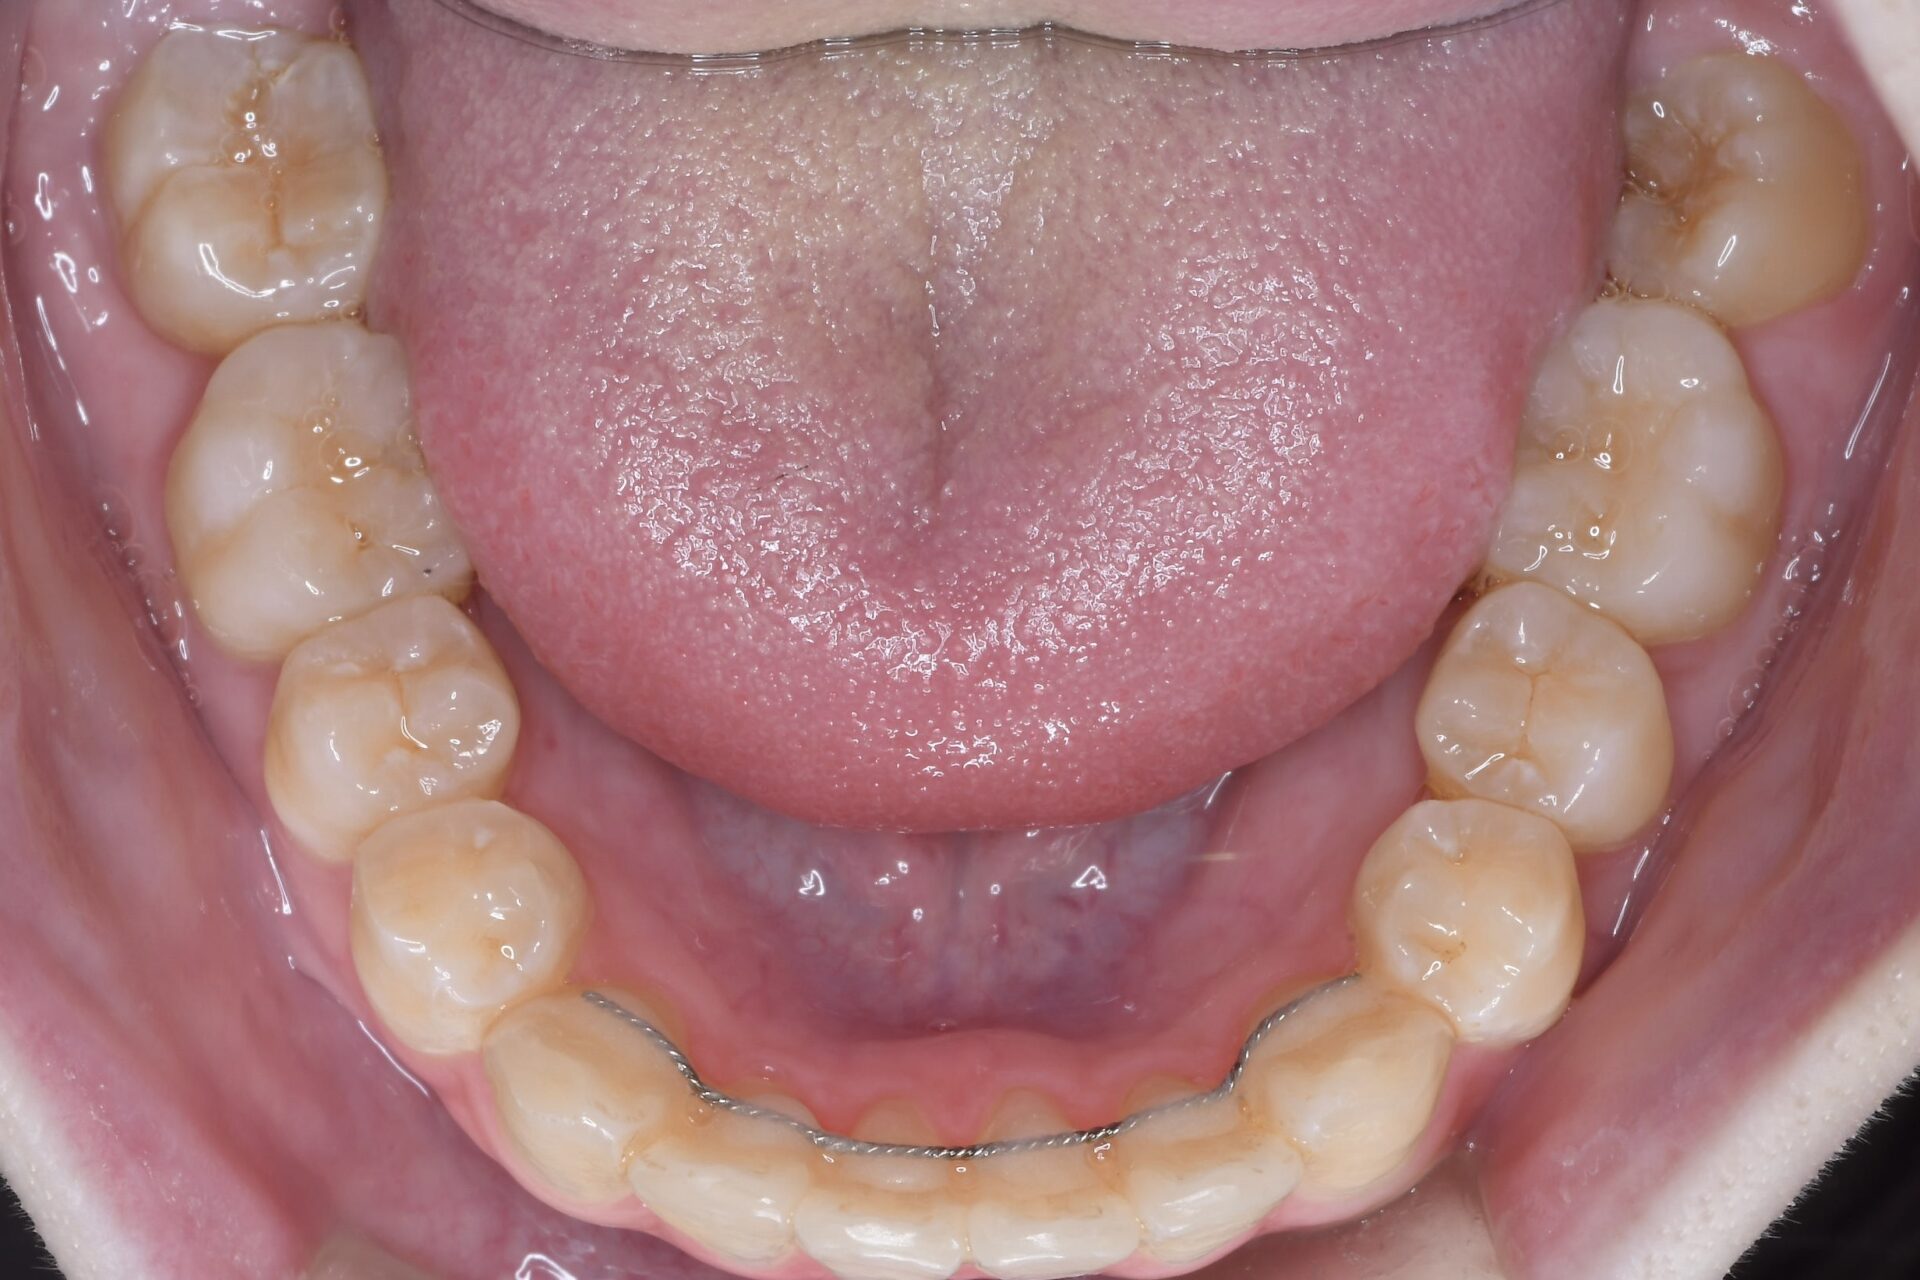

歯列矯正

多形腺腫が原因で咬合不全を起こしている全顎的矯正case

before

症例情報

主訴 歯並びを治したい 治療方法 全顎的矯正治療 年代 20代 性別 女性 費用 矯正治療費 ¥990.000 治療期間 矯正期間33ヶ月 来院回数 月1回 メリット 矯正治療により奥歯で均等に噛めるようになる。 リスク 埋伏している親知らずを利用するため矯正治療の期間が長くなってしまう。 -

初診時

奥歯だけが点で当たっていて、前歯が噛んでいない。

左側上顎第2大臼歯が随分と外側に生えている。そのため下顎とすれ違ってしまっていた。

口蓋に痛みはないが大きな腫れがある。その腫れのため大臼歯は外側に生えてきてその後も少しずつ動かされてしまったと思われる。矯正治療を進めても臼歯部はほとんど内側に動いてこない。生検により多形腺腫と診断される。